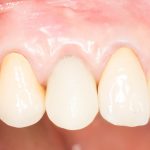

Рекомендации по установке имплантов. Для всех. Часть V.